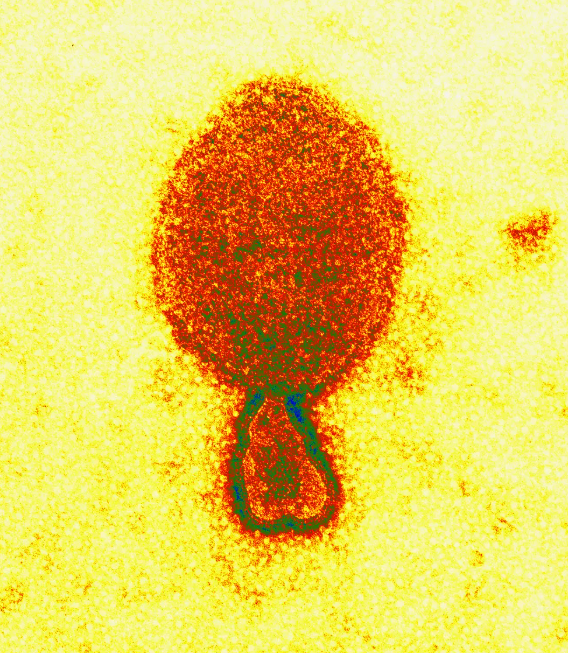

Novo vírus de origem animal infecta 35 pessoas na China (Foto: Reprodução)

Publicado na revista científica “New England Journal of Medicine”, na quinta-feira (4), um estudo científico feito na China anunciou a detecção de um novo tipo de vírus de origem animal, o henipavírus.

Já são 35 casos confirmados da doença que é  transmitida por morcegos frugívoros.